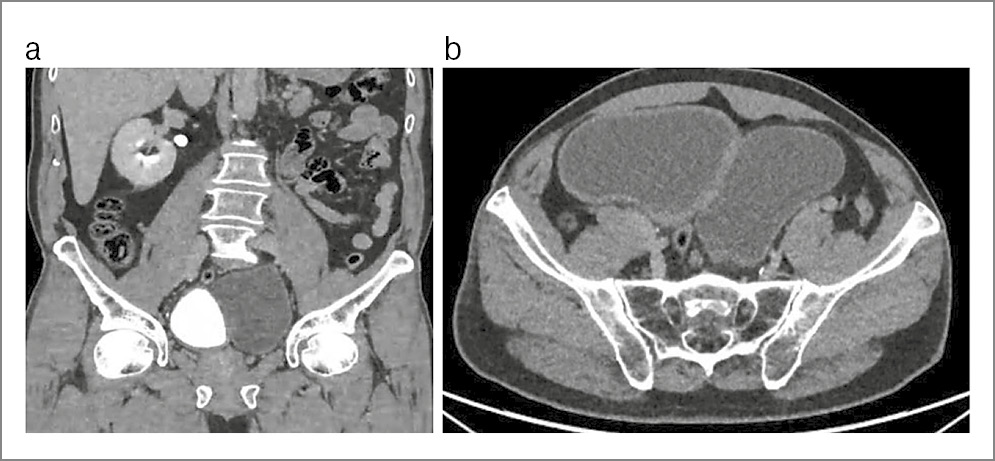

Наряду с ДМП выявлена аномалия в виде аплазии левой почки. В правой почке определена простая субкапсулярная киста объемом 15 см3. Объем предстательной железы составил 18,2 см3. При урофлоуметрии максимальная скорость мочеиспускания равнялась 15,0 мл/с, средняя – 8 мл/с при объеме мочеиспускания 210 мл. В перечень выполненных исследований вошли КТ живота и таза с контрастированием, микционная цистография и фиброуретроцистодивертикулоскопия. При последнем исследовании устье левого мочеточника не выявлено (рис. 3–6).

Рис. 3. Пациент В., компьютерная томограмма живота и таза: a – аплазия левой почки, ДМП; b – ДМП.